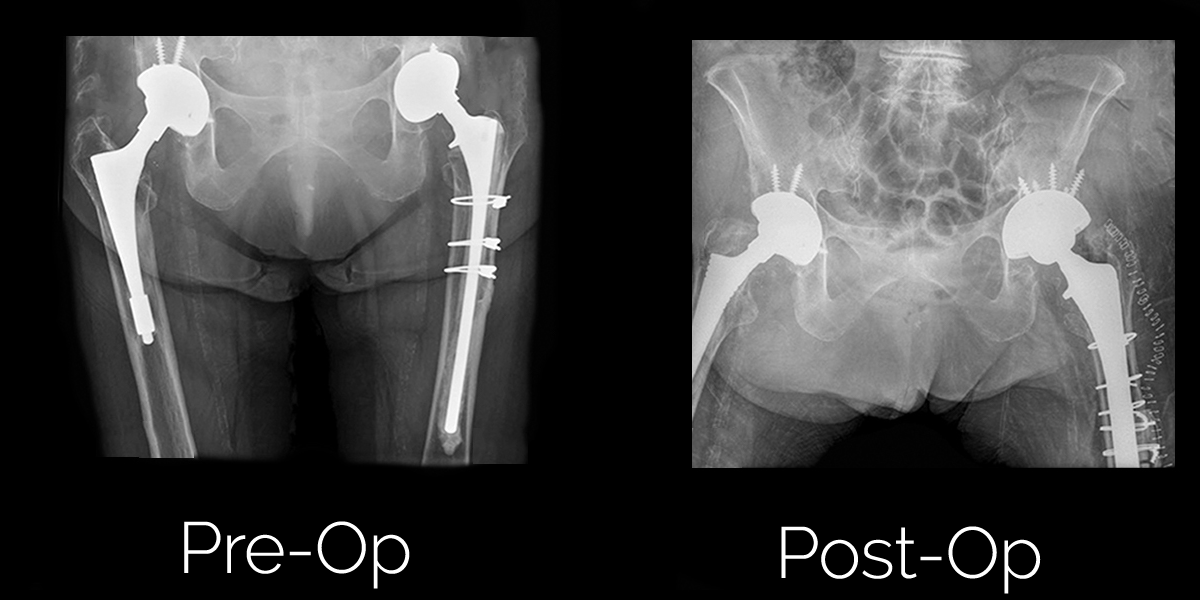

Revision Total Hip Replacement — Constant Busch

Revision Total Hip Replacement — Constant Busch Best Hip Replacement Revision Surgeons A knee or hip replacement surgery sometimes needs a “redo,” or revision, surgery. Typically, your primary care provider will refer you to doctor near me if they believe it to be necessary based on your symptoms or a. Revision total hip replacement is a more complex procedure and takes longer to perform than primary total hip replacement. Revision hip replacement,. Best Hip Replacement Revision Surgeons.

REVISION & COMPLEX REVISION ARTHROPLASTY Dr Andre Olivier Best Hip Replacement Revision Surgeons Yale medicine orthopedic surgeons discuss when to seek a second opinion. A preoperative aspiration (fluid sample) and/or special blood work may be needed if the surgeon suspects an infection in the failed hip. Typically, your primary care provider will refer you to doctor near me if they believe it to be necessary based on your symptoms or a. A hip. Best Hip Replacement Revision Surgeons.